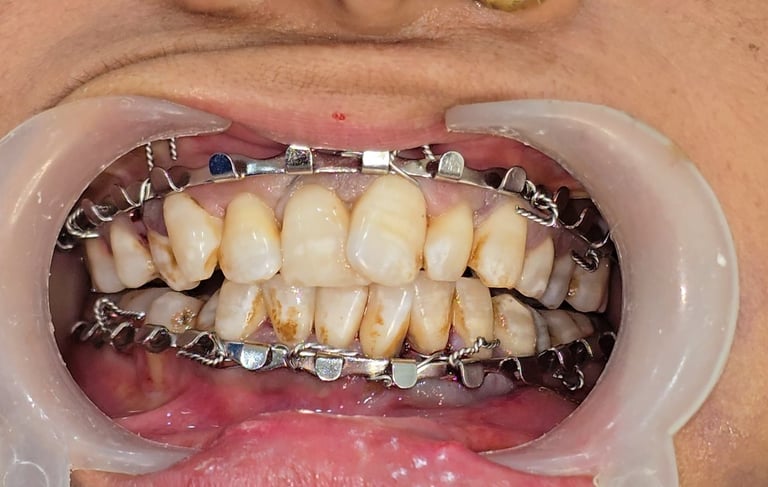

Initial Stabilization with Intermaxillary Fixation (IMF)

IMF was done to achieve temporary occlusion and stability.

Elastic bands were used to immobilize the segments.